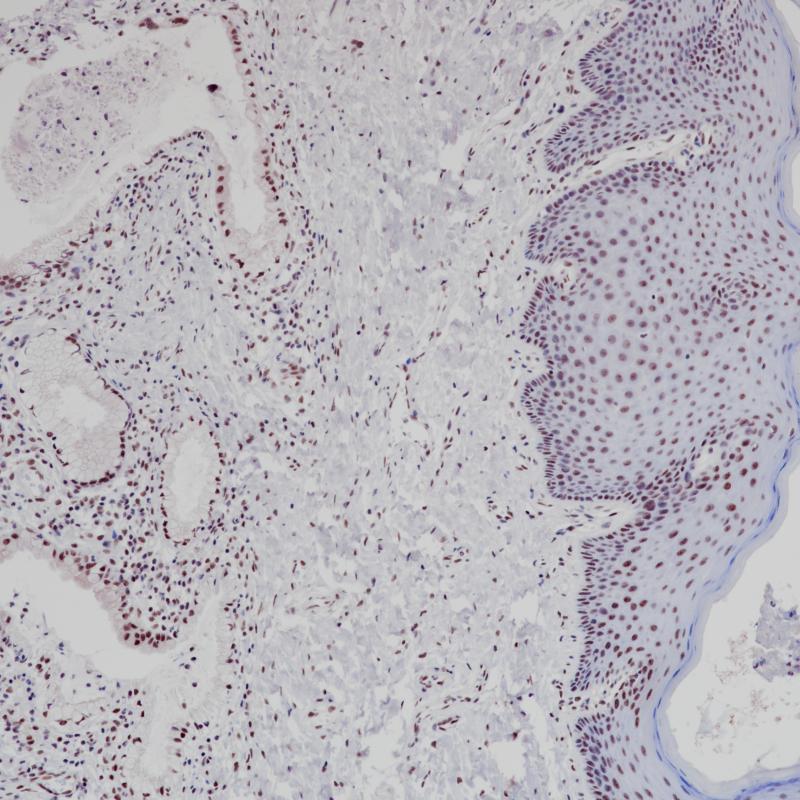

阳性对照

乳腺癌

亚细胞定位

细胞核